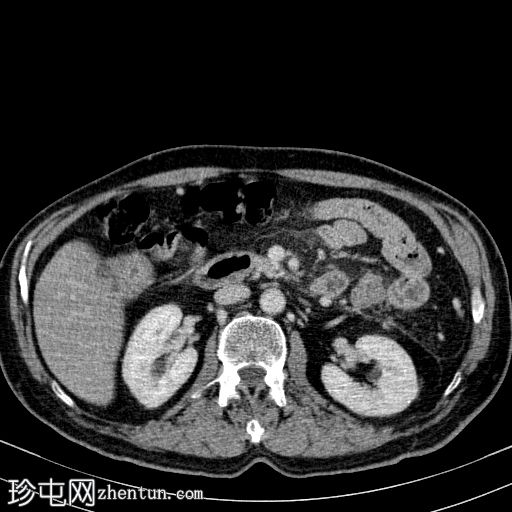

CT扫描

1.jpg

轴向

非造影

胰体尾弥漫性增大,特征为胰腺实质低强化,无明显坏死区域。

该病灶与以下表现相关:

胰周筋膜平面边界不清的污迹,无明显壁形成、气室、固体碎片或血液产物。

无肠系膜或脾脏血管阻塞的证据。

未见导管扩张或钙化。